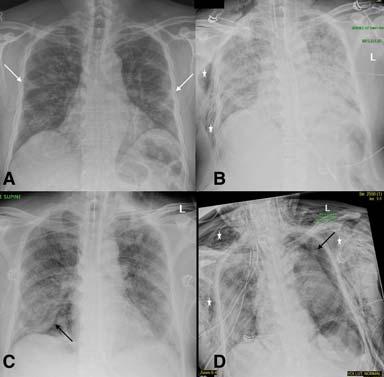

4 — CXR of a 71-year-old man with 4 days history of shortness of breath. Classical features of hazy opacities are seen in the lower lobes bilaterally in a peripheral distribution. Image reproduced with permission from Covid-19 Database of the Fleischner Society.

Fig 5 — CXR’s of different patients with proven COVID-19 demonstrating varied appearances at the time of presentation. ANo abnormalities could be seen on CXR and the corresponding CT (not shown) was also near normal. B- Ill-defined hazy peripheral opacities seen in the left upper zone. C- Multifocal opacities were seen in the right lung on CXR at presentation. D- CXR showing extensive parenchymal infiltrates in a patient who came to the hospital in very bad respiratory distress and was found to have COVID-19 on testing.

Fig 6 — Serial CXR’s of a patient with COVID-19 showing development of atypical findings during the admission. The admission radiograph (A) demonstrates multifocal peripheral opacities (white arrow), followed by the development of right pneumothorax (black arrow) on day 7 (B) of admission with improvement in parenchymal changes subsequently on day 15 of admission (C). He developed extensive left pneumothorax (black arrow) and surgical emphysema (star)(D)of the chest wall later in the course. Images courtesy of Dr Amrita Bajaj, Glenfield Hospital, Leicester.

Fig 8 — Serial CXR examinations in a patient showing disease progression. Presentation (A) film had bilateral peripheral hazy opacities that increased on day 7 (B) and became confluent. Further worsening of parenchymal changes on day 11 with the patient requiring extracorporeal membrane oxygenation (ECMO) support (C) with improvement in clinical condition and persistent parenchymal fibrotic infiltrates on day 23 of admission (D). Images courtesy of Dr Amrita Bajaj, Glenfield Hospital, Leicester.

Fig 9 — Serial CXR examinations in a patient who succumbed to the infection. This patient came in with severe respiratory distress and was put on ventilator support early in his admission. ECMO therapy was also started (A) with bilateral parenchymal consolidation. Patient kept deteriorating on ECMO (Day 13- B, Day 18 C and Day 27- D) and succumbed to the disease. Images courtesy of Dr Amrita Bajaj, Glenfield Hospital, Leicester.